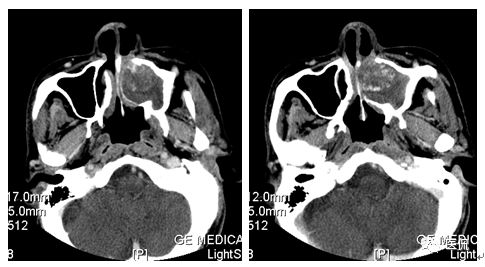

增强水平位FST1WI

CT平扫及增强示:左侧上颌窦及鼻腔可见软组织密度影,呈膨胀性生长,周围骨质压迫性吸收破坏,累及左眶,病灶密度不均匀,周边区可见点状钙化,增动脉期轻度强化,局部见小灶性稍高密度区,静脉期病灶内见不均匀明显强化,CT值最高达117HU,延迟期强化范围有所增大。

影像学表现呈软组织密度,多不均匀,表现为高低混杂密度,病变窦腔内息肉、血肿、坏死、感染共存,是病灶密度不均匀的主要原因,息肉反复出血、血管机化亦为其成因之一。病灶内钙化,可为团块状或小片状,可能为病变组织坏死后钙质沉着所致。由于病变组织内有大量炎性细胞浸润和丰富的毛细血管,增强后常有强化。有文献报道病灶增强中心区强化不明显,外周呈轻度强化,推测病灶内虽然血管丰富,但中心区容易出现血流动力学障碍,血管内常有血栓形成,中心区易发生出血坏死,另外,可能与增强扫描延迟时间选择不当有关。

本例病灶较大,周围骨质可见吸收破坏,并累及眼眶,病灶内少量钙化,增强扫描具有一定特征性,表现为动脉期轻度强化,局部见小灶性稍高密度区,静脉期病灶局部呈明显强化,CT值最高达117HU,延迟期强化范围有所增大,呈延迟渐进性强化的特点,推测为病灶内出血所致。